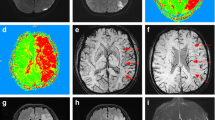

All images were collected from our picture archiving and communication system as DICOM-format data and imported to an Osirix image viewer (Version 3.8.1, 32 bit) on an Apple iMac for analysis. A 10-point semi-quantitative CT scoring system, Alberta Stroke Program Early CT Score (ASPECTS) [14], was used to assess the size abnormal signal intensities or densities on individual DWI, SWI, PWI and FI studies. Two neuroradiologists (H.W.K. and F.Y.T.), blinded to patient information except for the clinical history of ischaemic stroke, independently assessed ASPECTS values on the selected images. For calculating ASPECTS values, 1 point was subtracted from 10 for an area of ischaemic changes, including restricted diffusion, asymmetric prominent vessels on SWI, prolonged MTT, reduced rCBF and rCBV, hyperintensity on FLAIR images and hypointensity on CT (Fig. 1). Image contrast and brightness were optimised between areas of ischaemic changes and normal-appearing brain.

Figure 2 gives an overview of the ASPECTS values on various imaging parameters after grouping patients into IG and NIG groups. A significant difference in ASPECTS values among the parameters was found in the IG group (P < 0.001), but not in the NIG group (P = 0.202). In the IG group, the DWI ASPECTS values were not significantly different from rCBF and rCBV values (P = 0.368). The SWI ASPECTS values were not significantly different from MTT and FI values (P = 0.779), but significantly lower than DWI values (P = 0.028).

Table 2 shows correlations among various imaging parameters. There were significant correlations in the ASPECTS values among all initial imaging parameters and FI studies. The rCBF was the most accurate parameter to predict FI (ρ = 0.875, P < 0.001). The ASPECTS values on SWI correlated significantly with those on other initial imaging parameters, best with the values on MTT (ρ = 0.8, P < 0.001, Fig. 3).